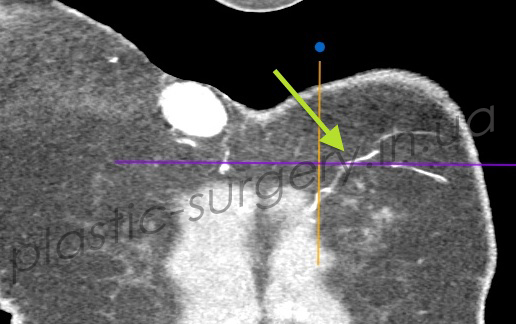

После предварительной локации точки выхода сосудов в покровные ткани в области поясницы, рядом с раневым дефектом с помощью аудио-допплера, больному было проведено более детальное обследование – КТ с ангиографией. При проведении исследования была визуализирована одна из люмбальных артерий и её перфорант справа от позвоночника, уточнено место выхода перфоранта, направление его оси и ветвление в покровных тканях (Рис. 3, 4, 5).

Рис. 3. Снимок компьютерной томографии с ангиографией, стрелкой отмечена люмбальная артерия. (слева).

Рис. 4. Снимок компьютерной томографии с ангиографией, стрелкой отмечена люмбальная артерия и её перфоранты, выходящие в покровные ткани. (справа).

Рис. 5. Снимок компьютерной томографии с ангиографией. Визуализируется перфорант люмбальной артерии, направление его оси, ветвление артерии в покровных тканях.